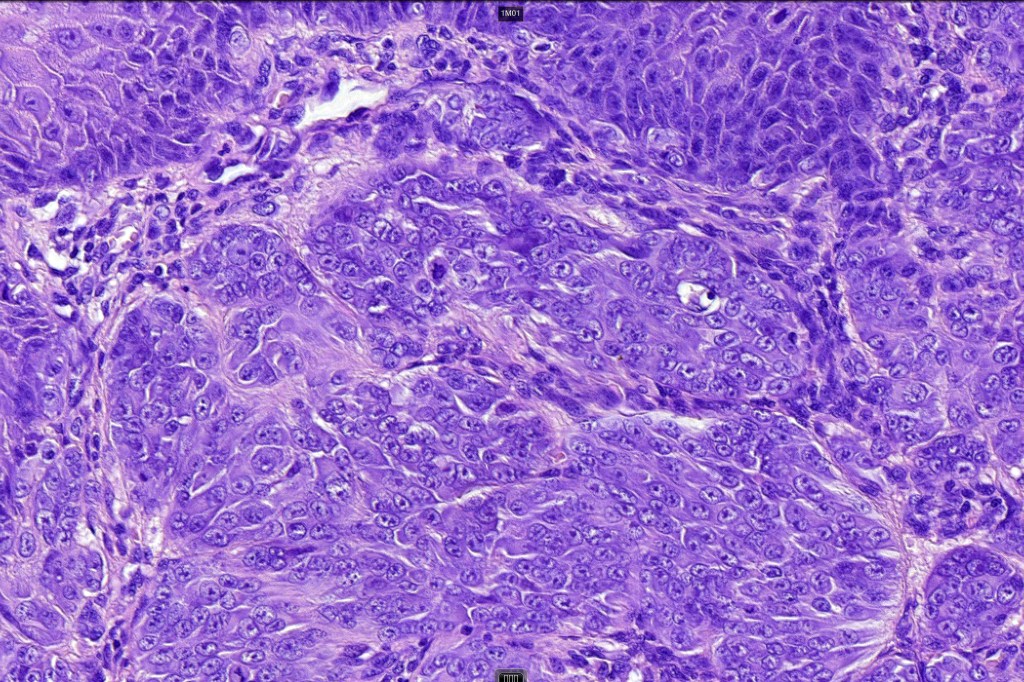

Histological features

•Large nodules which often show impaired maturation

•Loss of gradient with HMB45 and Ki67

•>20% Ki67 expression